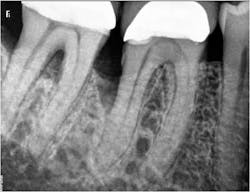

In the present case, a 61-year-old male was referred to my periodontal office by his general dentist for an evaluation of pain and bleeding to the lower right mandible. The patient’s medical history consisted of controlled type 2 (noninsulin dependent) diabetes and hypertension. Upon review of the panoramic radiograph (figure 1), the periodontal defects are not clearly evident, thus showing the importance of proper radiographs to detect periodontal defects. The periapical radiographs (figure 2) clearly show subgingival calculus, grade 1 furcation on No. 30, grade 3 furcation on No. 31, and an advanced intrabony defect on the distal of No. 30. Clinically, there was no mobility to either No. 30 or 31 and both teeth were vital. Tooth vitality is an extremely important diagnostic factor in treatment panning. Periodontal charting of the lower right was also performed, and the lower right exhibited bleeding and inflammation (figure 3).